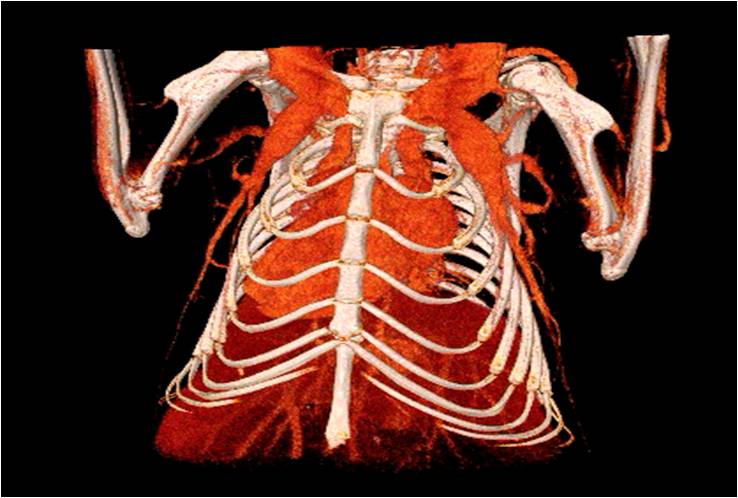

心血管

胸部和心血管的層析成像                                       胸部和心血管的3D圖像

心血管.jpg     心血管1.jpg